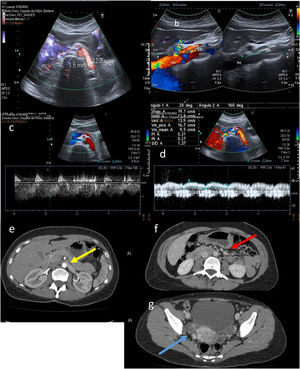

A) Morfología en gancho del tronco celiaco con cambio en la orientación en relación con la inspiración y la espiración. B) Tronco celiaco con elevación de las velocidades en el pico sistólico > 200 cm/s. C) En espiración, la velocidad asciende de 192 hasta 322 cm/s. D) Angio-TC: (espiración) estenosis focal de la porción proximal del tronco celiaco (apariencia en gancho). E y F (detalle): angio-TC (fase arterial) donde se visualiza el signo del “moño y la mantilla”. G) Signo del “moño y la mantilla”.

Para el diagnóstico, si observamos una elevación de las velocidades en el pico sistólico en espiración máxima superior a 200cm/s con índice tronco celiaco/aorta > 3, estaremos ante un compromiso del flujo significativo (fig. 6 B y C).

A menudo es necesaria la realización de una angio-TC para valorar el grado de estenosis. Es característica la impronta superior en el origen del tronco celiaco, que adopta una morfología en “gancho” o “garfio”. Otro hallazgo radiológico es el signo del “moño y la mantilla”, que consiste en la visualización, en un mismo plano axial, del tronco celiaco comprimido y deformado entre la aorta abdominal ubicada dorsalmente y el ligamento arcuato mediano localizado ventralmente, el cual rodea prácticamente a los otros dos. Estos hallazgos asemejan una cabeza (aorta) tocada con un moño (origen del tronco celiaco) y cubierta por un paño (ligamento arcuato mediano). Este permite establecer el diagnóstico en estudios no dirigidos y la selección de los pacientes a los que completar estudios8.

A) Calibre de la vena renal izquierda (VRI) en región hiliar (antes de la pinza): 12,2mm. Calibre VRI en la propia pinza entre la aorta (Ao) y la arteria mesentérica superior (AMS): 1,5mm. B) Ángulo aortomesentérico a nivel de VRI disminuido (20°). C) Velocidad de la VRI aumentada en la pinza aortomesentérica (106cm/s). D) Velocidad normal de la VRI previa a la pinza (19cm/s). E-G) Proyecciones axiales de tomografía computarizada de abdomen con contraste en fase arterial (E) y fase portal (F y G). En la imagen E se observa una reducción del calibre de la VRI al pasar por la pinza aortomesentérica (flecha amarilla). En la imagen F se aprecian venas gonadales ligeramente dilatadas (flecha roja). En la imagen G son visibles varices parauterinas derechas (flecha azul).

Se considera anormal un valor de velocidad máxima de la vena renal en la pinza mayor de 100cm/s (criterio no imprescindible). Una ratio distal/proximal > 5 es diagnóstica para este síndrome (fig. 8 C).